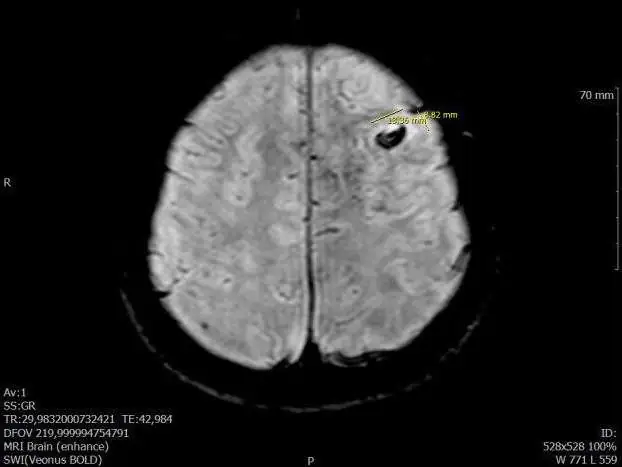

В инсультном центре мне сделали магнитно-резонансную томографию (МРТ). Она показала доброкачественную опухоль — кавернозную гемангиому. Врач предположил, что все симптомы были связаны с ней.

В больнице в первый же день у меня взяли анализы крови, мочи, сделали компьютерную томографию, магнитно-резонансную томографию, сняли электрокардиограмму. В общем, провели полное обследование для постановки диагноза и подготовки к операции.

Перед операцией проведут компьютерную нейронавигацию: по КТ и МРТ хирург спланирует каждое действие с точностью до миллиметра. После чего опухоль удалят методом keyhole surgery («хирургия замочной скважины»).

11 ноября пришел в последний раз в больницу, чтобы снять швы. Мне сделали повторное МРТ и прописали противоэпилептические лекарства — по протоколу их надо принимать полгода. Результаты полного иммуногистохимического и генетического исследования опухоли обещали прислать по электронной почте.

Уже дома я получил письмо о том, что у меня был рак в начальной стадии — диффузная астроцитома. Оказалось, что она находилась в том же месте, где и моя доброкачественная опухоль. Можно сказать рак был скрыт под ней, поэтому на МРТ его не видно.

Результаты анализов показывают наличие раковой опухоли diffuse astrocytoma — диффузная астроцитома

Скорее всего, эпилептические припадки и головные боли были связаны с онкологией, а не доброкачественной опухолью. Получилось, что я приехал лечить одну болезнь, а вылечил другую — гораздо более опасную.

Теперь мне всю жизнь нужно регулярно делать МРТ головного мозга. Первое обследование сказали сделать через полгода. Я могу делать МРТ в Казахстане и отправлять снимки в Корею, или сразу обследоваться в Корее, на мой выбор.